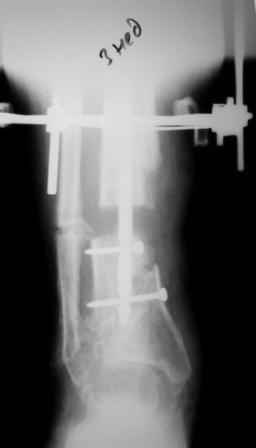

2) После репозиции более очевидна стала проблема дефекта кости в верхней трети голени, два фрагмента свободно лежат. Остановились на варианте перехода на интрамедуллярный синтез стержнем с покрытием костный цемент+ванкомимцин и замещении дефекта с помощью транспорта фрагмента (рис 2)